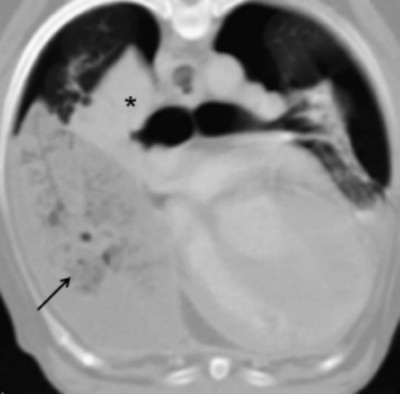

患有右中叶部分扭转的犬仅表现为受累肺叶的肺不张,但支气管位置和气体含量正常(图6)。该犬也存在胸腔积液和气胸。

图 6. 一只6岁混种犬患有右中叶部分扭转。背侧重建CT图像(A),左侧卧位横断图像(B)以及图6B所示平面的斜位重建图像(C)。右中叶(*)塌陷,支气管弯曲,但在重建图像中整个支气管可见且充满气体。